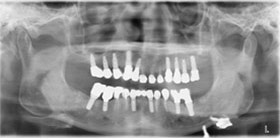

1. 治療前X光片,多處缺牙及嚴重牙周破壞。

proimages/case/Artificial_implant/all-1.jpg